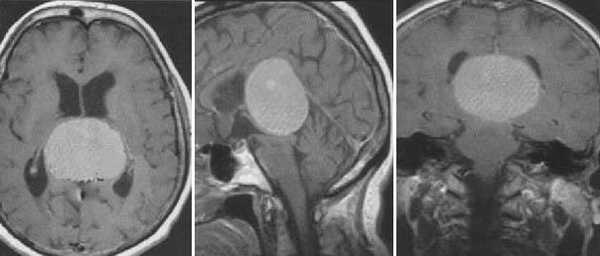

Пинеоцитома. МРТ в режиме Т2 и Т1 выявляется солидного строения опухоль задних отделов III желудочка мозга. На фоне в/в контрастирования определяется выраженный и достаточно гомогенный характер контрастирования опухоли.

Пинеобластома. В режиме Т2 и Т1 выявляется опухоль задних отделов III желудочка мозга с развитием окклюзионной гидроцефалии. В строме опухоли небольшой участок подострого кровоизлияния. После в/в контрастирования опухоль интенсивно и достаточно гомогенно накапливает контрастирующее вещество.